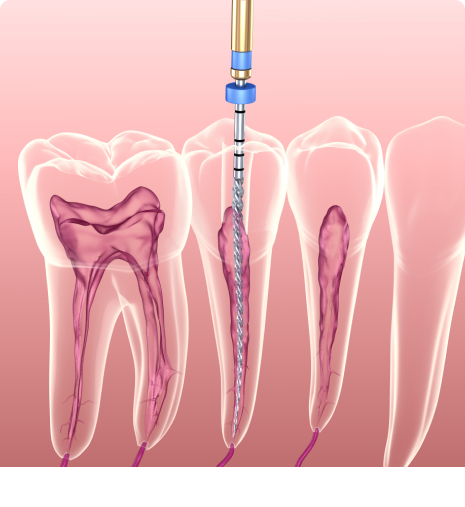

Every tooth is a three-layered structure namely – Enamel, Dentin & Pulp. If the tooth decay is limited to the first two layers, it can be corrected with Filling/ Restoration. In case the tooth decay reaches the third layer and causes inflammation or infection of pulp, an RCT or Endodontic Treatment is needed. Read More